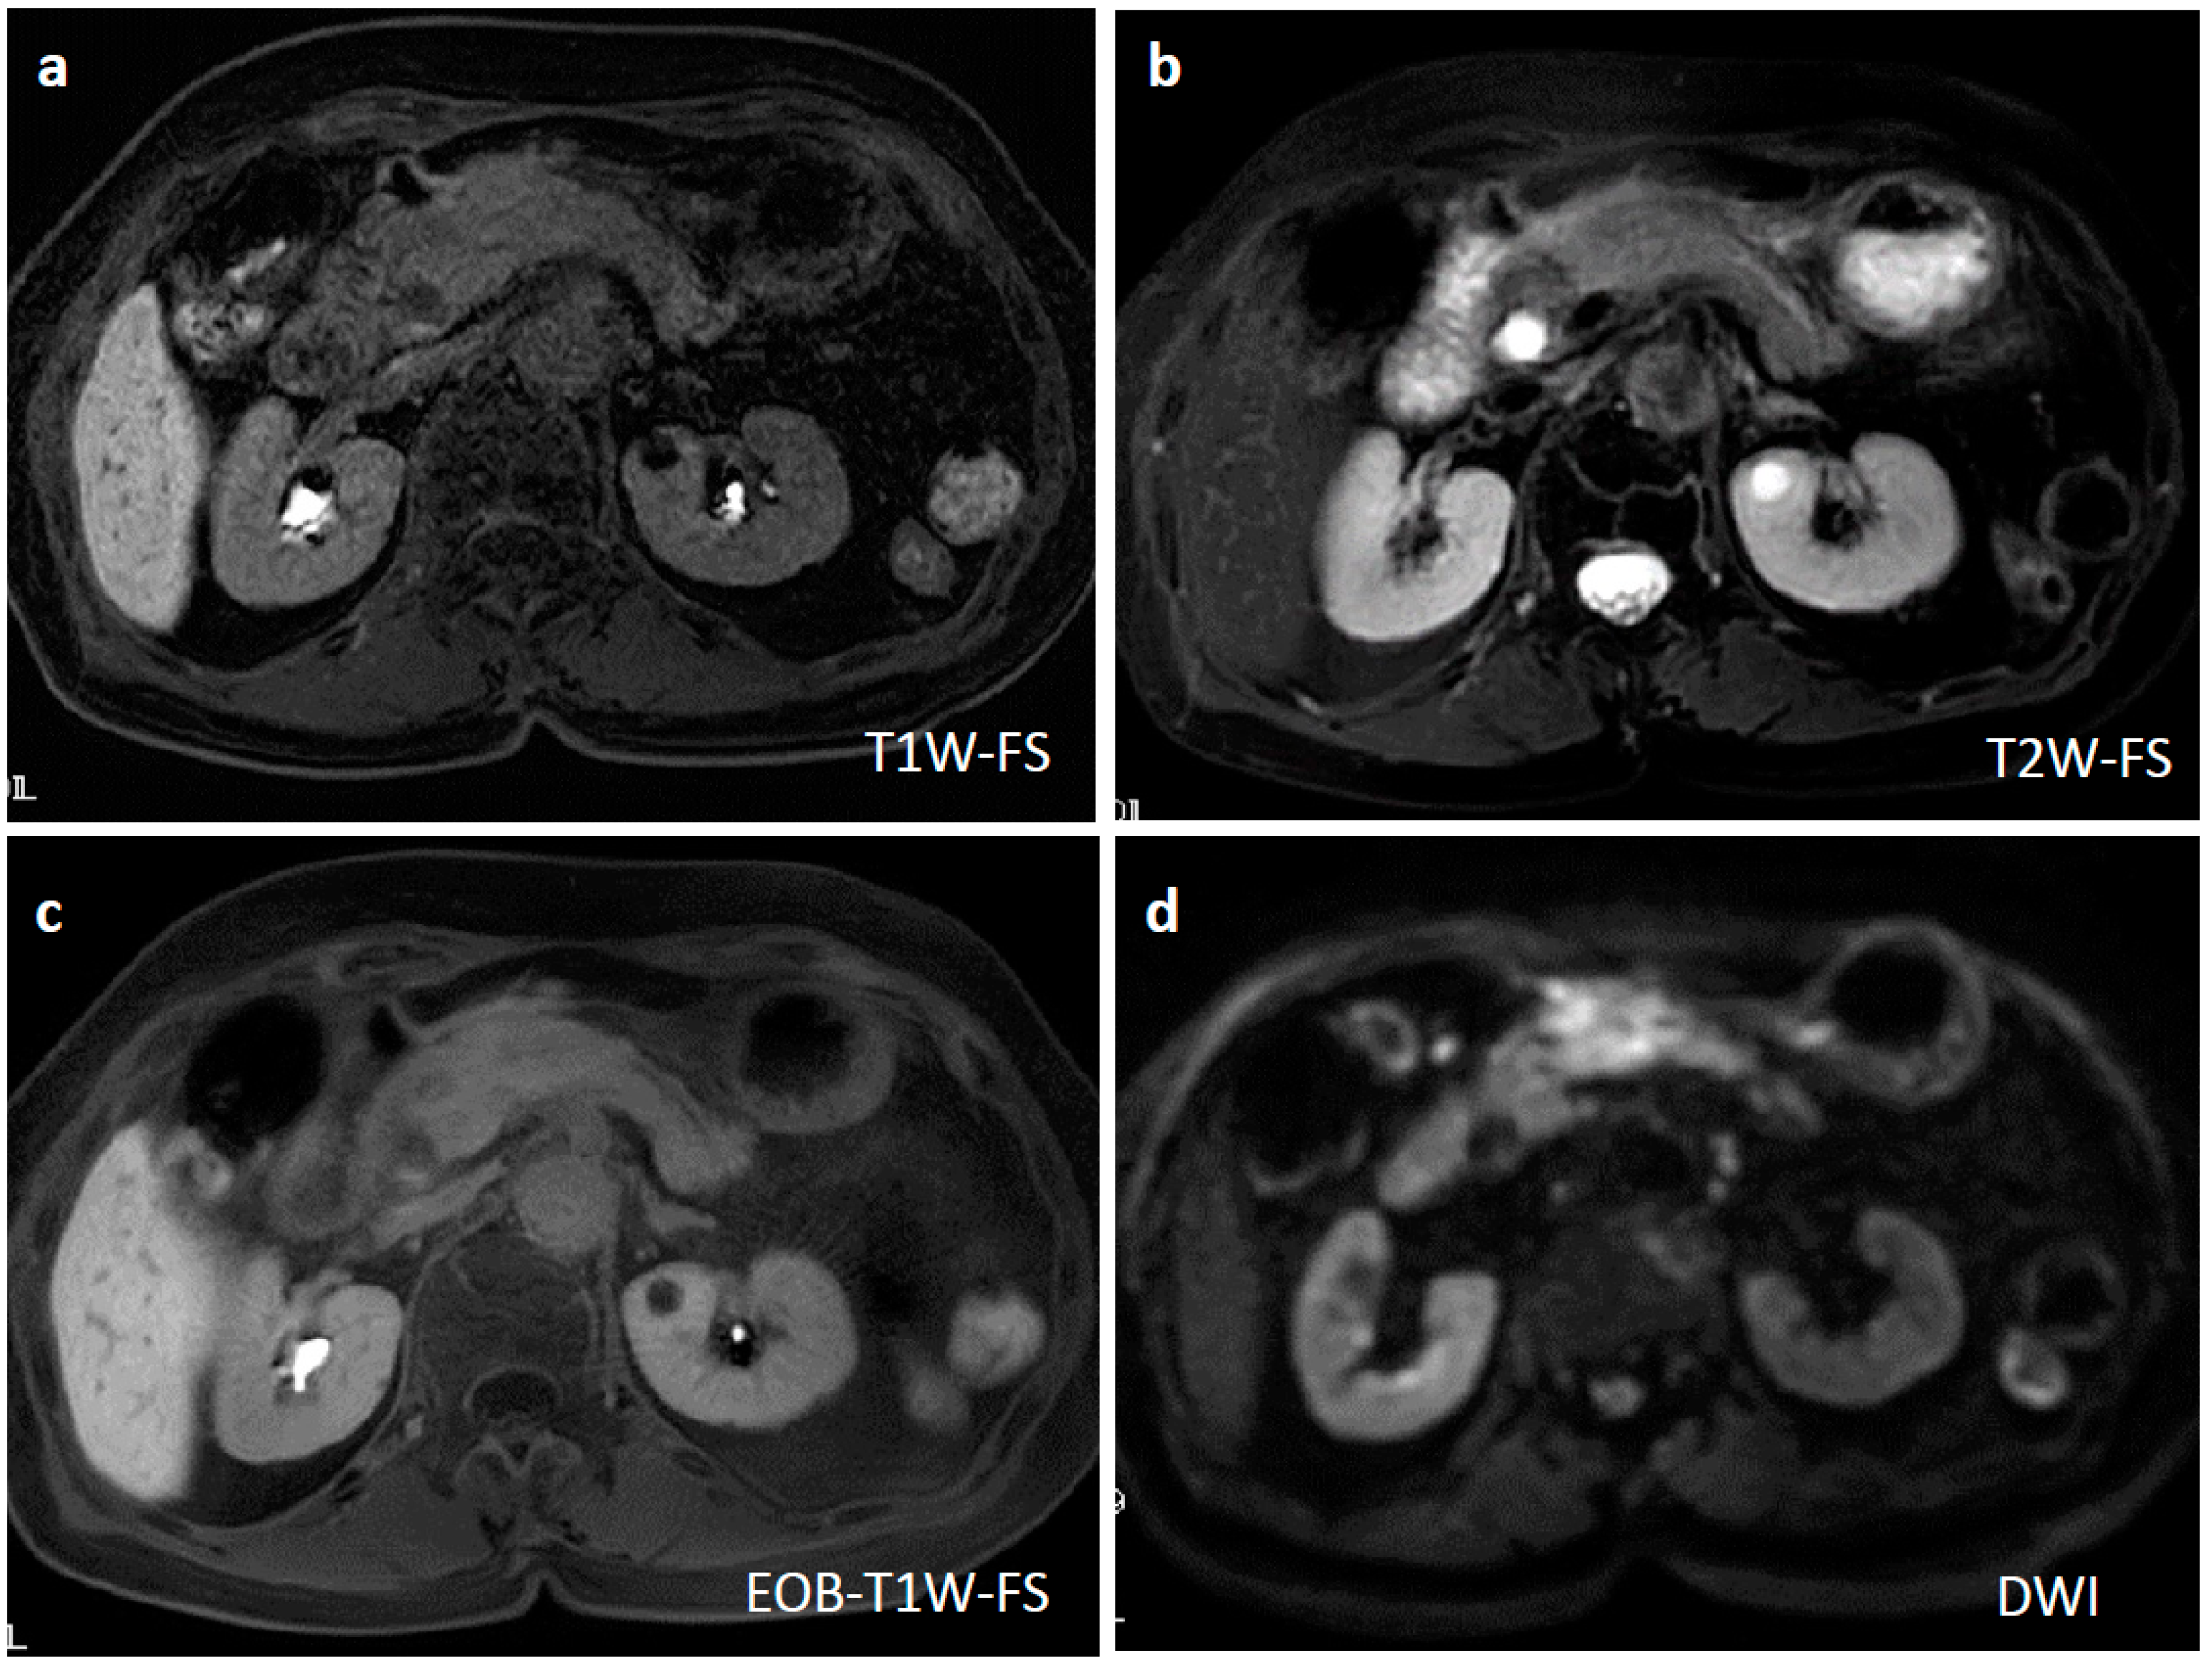

Figure 1.

Enhanced computed tomography. An irregular-margined, low-attenuated mass 5 cm in size was seen at the pancreas head (horizontal view (a), coronal view (b)). One month after the histological diagnosis, the pancreatic mass was markedly shrunken spontaneously (horizontal view (c), coronal view (d)).

Ten days after FNAB, positron emission tomography showed abnormal 18F-fluorodeoxyglucose uptake (SUVmax: 6.95); however, the pancreatic lesion seemed to have shrunk to 2.5 cm in size (Figure 5). Magnetic resonance imaging (MRI) demonstrated an obviously minimized tumorous lesion at the pancreas head (Figure 6). The mass lesion was visible as an iso-intensity signal in a T1-weighted image and as a faintly low-intensity signal in a T2-weighted image, while it was ill enhanced in an EOB image and the signal was heterogeneously repressed in a diffusion-weighted image. A subsequent CT, conducted one month after the FNAB, revealed further minimization of the pancreatic mass (Figure 1c,d). The images obtained in the next two months showed that the tumor had almost vanished. The tumor was no longer visible at the sixth month. During the post-diagnosis course, no medication was administered other than regularly taken hypotensive drugs. A written informed consent was obtained from the patient.